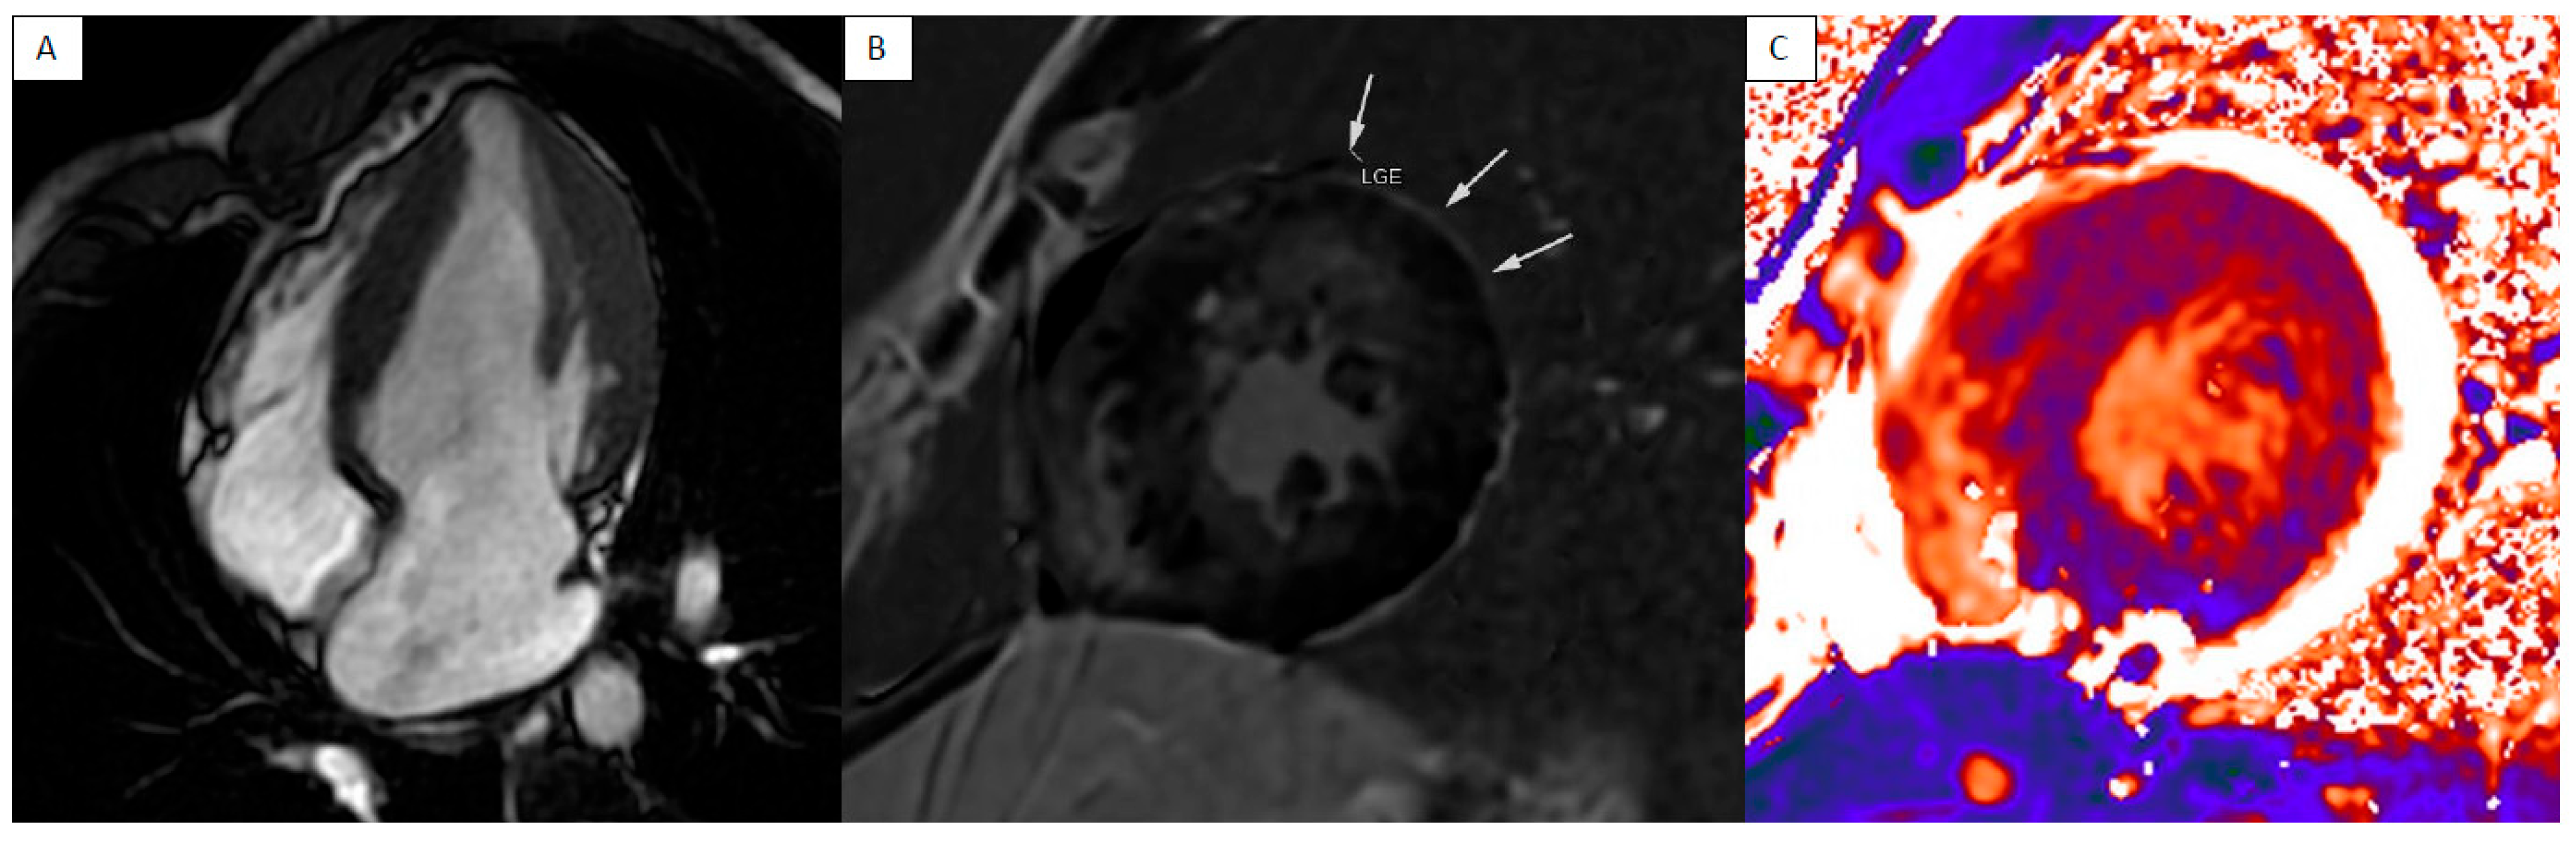

5. Anderson–Fabry Disease